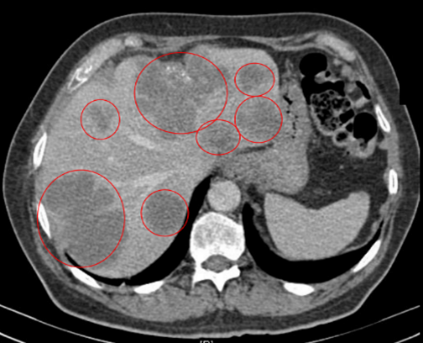

Vad visar bilden?

• Levermetastaser inringat

• Ljusa stråk är levervener